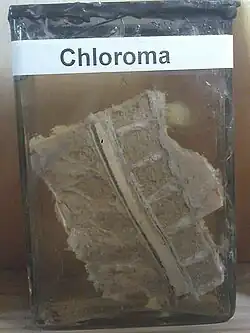

A myeloid sarcoma (chloroma, granulocytic sarcoma,[1]: 744 extramedullary myeloid tumor) is a solid tumor composed of immature white blood cells[2] called myeloblasts. A chloroma is an extramedullary manifestation of acute myeloid leukemia; in other words, it is a solid collection of leukemic cells occurring outside of the bone marrow.

The condition now known as chloroma was first described by the British physician A. Burns in 1811,[14] although the term chloroma did not appear until 1853.[15] This name is derived from the Greek word chloros (green), as these tumors often have a green tint due to the presence of myeloperoxidase. The link between chloroma and acute leukemia was first recognized in 1902 by Dock and Warthin.[16] However, because up to 30% of these tumors can be white, gray, or brown rather than green, the more correct term granulocytic sarcoma was proposed by Rappaport in 1967[17] and has since become virtually synonymous with the term chloroma.